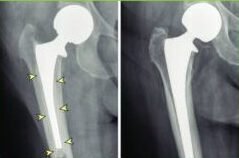

Cemented and Uncemented Hip Replacement are two surgical techniques used to replace the damaged hip joint with artificial components. In Cemented Hip Replacement, a special bone cement is used to fix the artificial components to the patient’s natural bone. Uncemented Hip Replacement, on the other hand, relies on the bone’s natural ability to grow and bond with the implants over time. The choice between cemented and uncemented techniques depends on various factors, including the patient’s age, bone quality, and surgeon’s recommendation.

2. Cemented Hip Replacement: If Cemented Hip Replacement is recommended, our skilled surgeons will use bone cement to fix the artificial components to your natural bone. This technique provides immediate stability and allows for early weight-bearing. It is often preferred for patients with weaker bone quality or certain medical conditions.

3. Uncemented Hip Replacement: If Uncemented Hip Replacement is the optimal choice for you, our surgeons will utilize implants that have a porous surface designed to encourage natural bone growth and integration. Over time, the patient’s bone will grow and bond with the implants, providing long-term stability and durability.